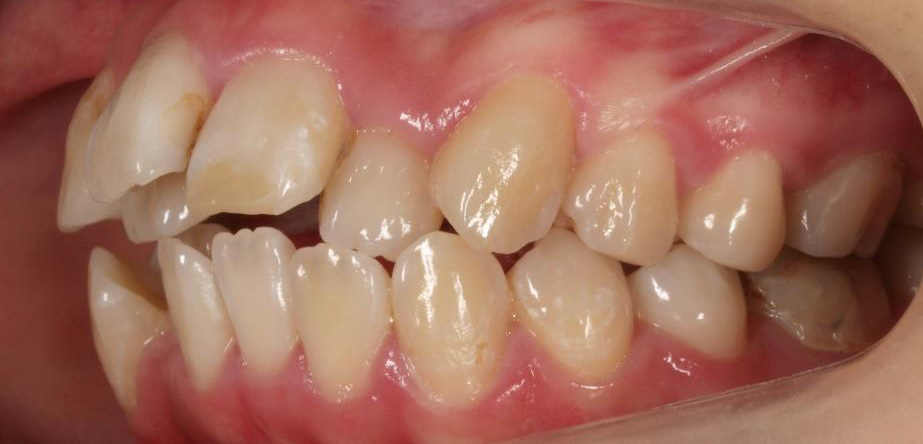

乱ぐい歯、でこぼこがとても酷い状態になります。歯が前後的に重なってしまっている、八重歯になっているなどがこのジャンルに入ります。

顎の大きさと歯の大きさのギャップが大きく、時には歯を抜かないと矯正治療ができない場合もあります。当院では治療期間が長くなるが抜かない治療方針など、一つの治療プランだけでなく、さまざまな可能性の治療方針を説明させて頂くよう心掛けております。こういった考え方はインフォームド・チョイスと言われ近年大切にされている考え方と言われております。

治療前

治療終了前